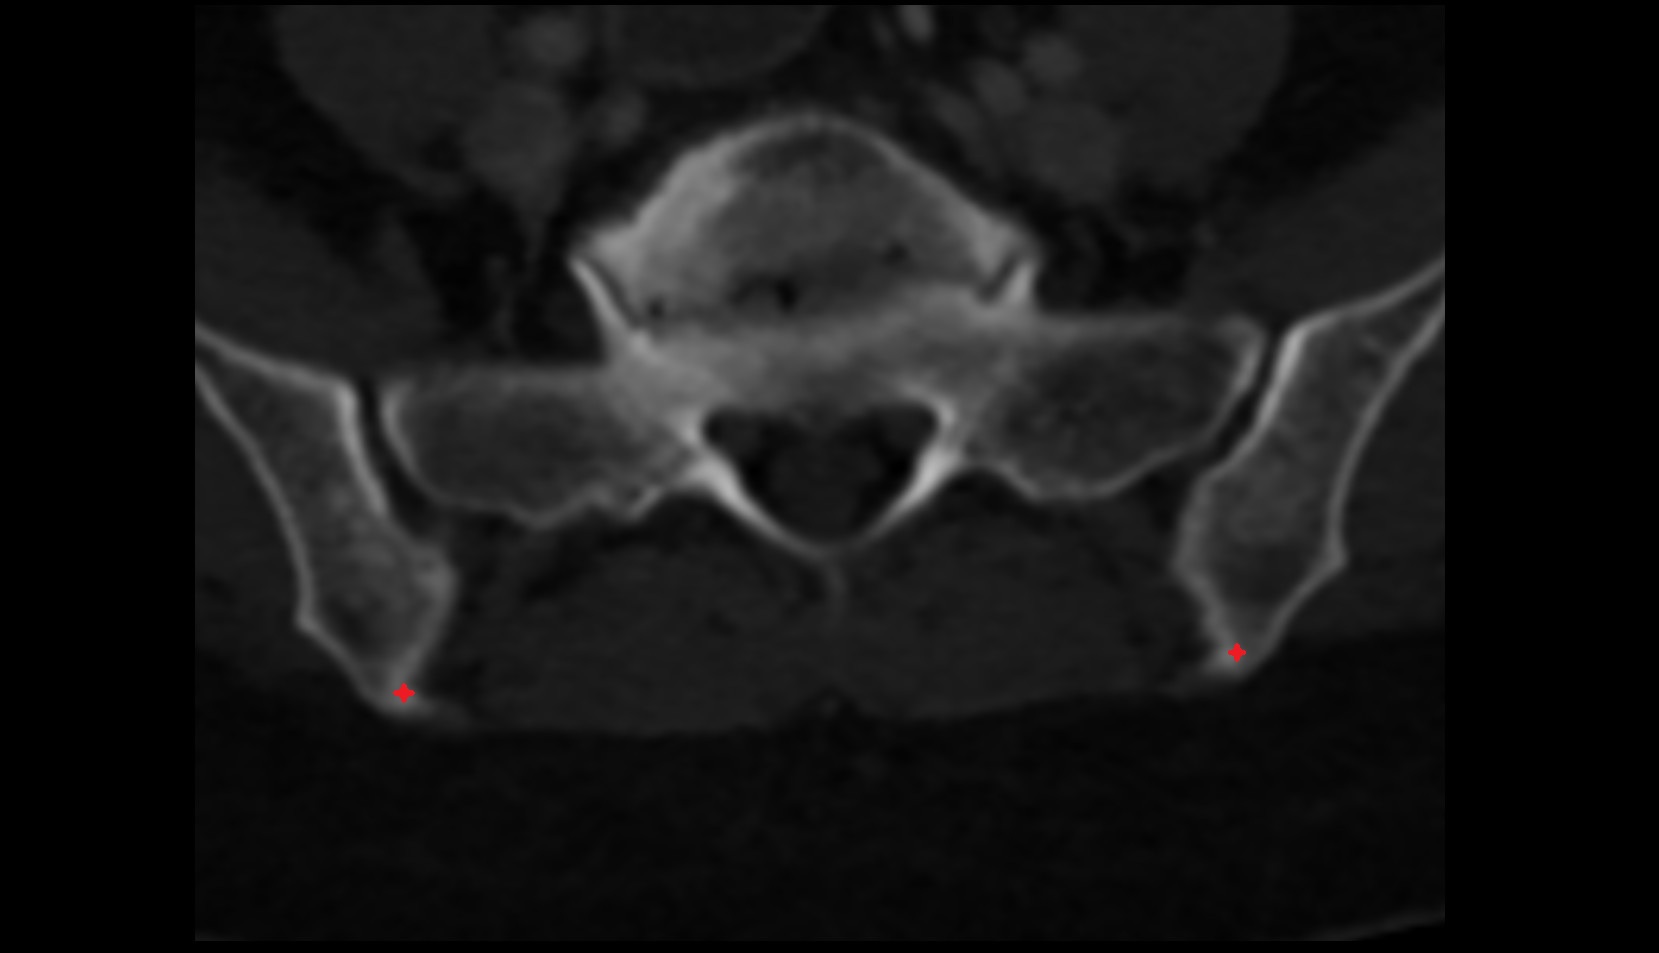

- Sacroiliac joint